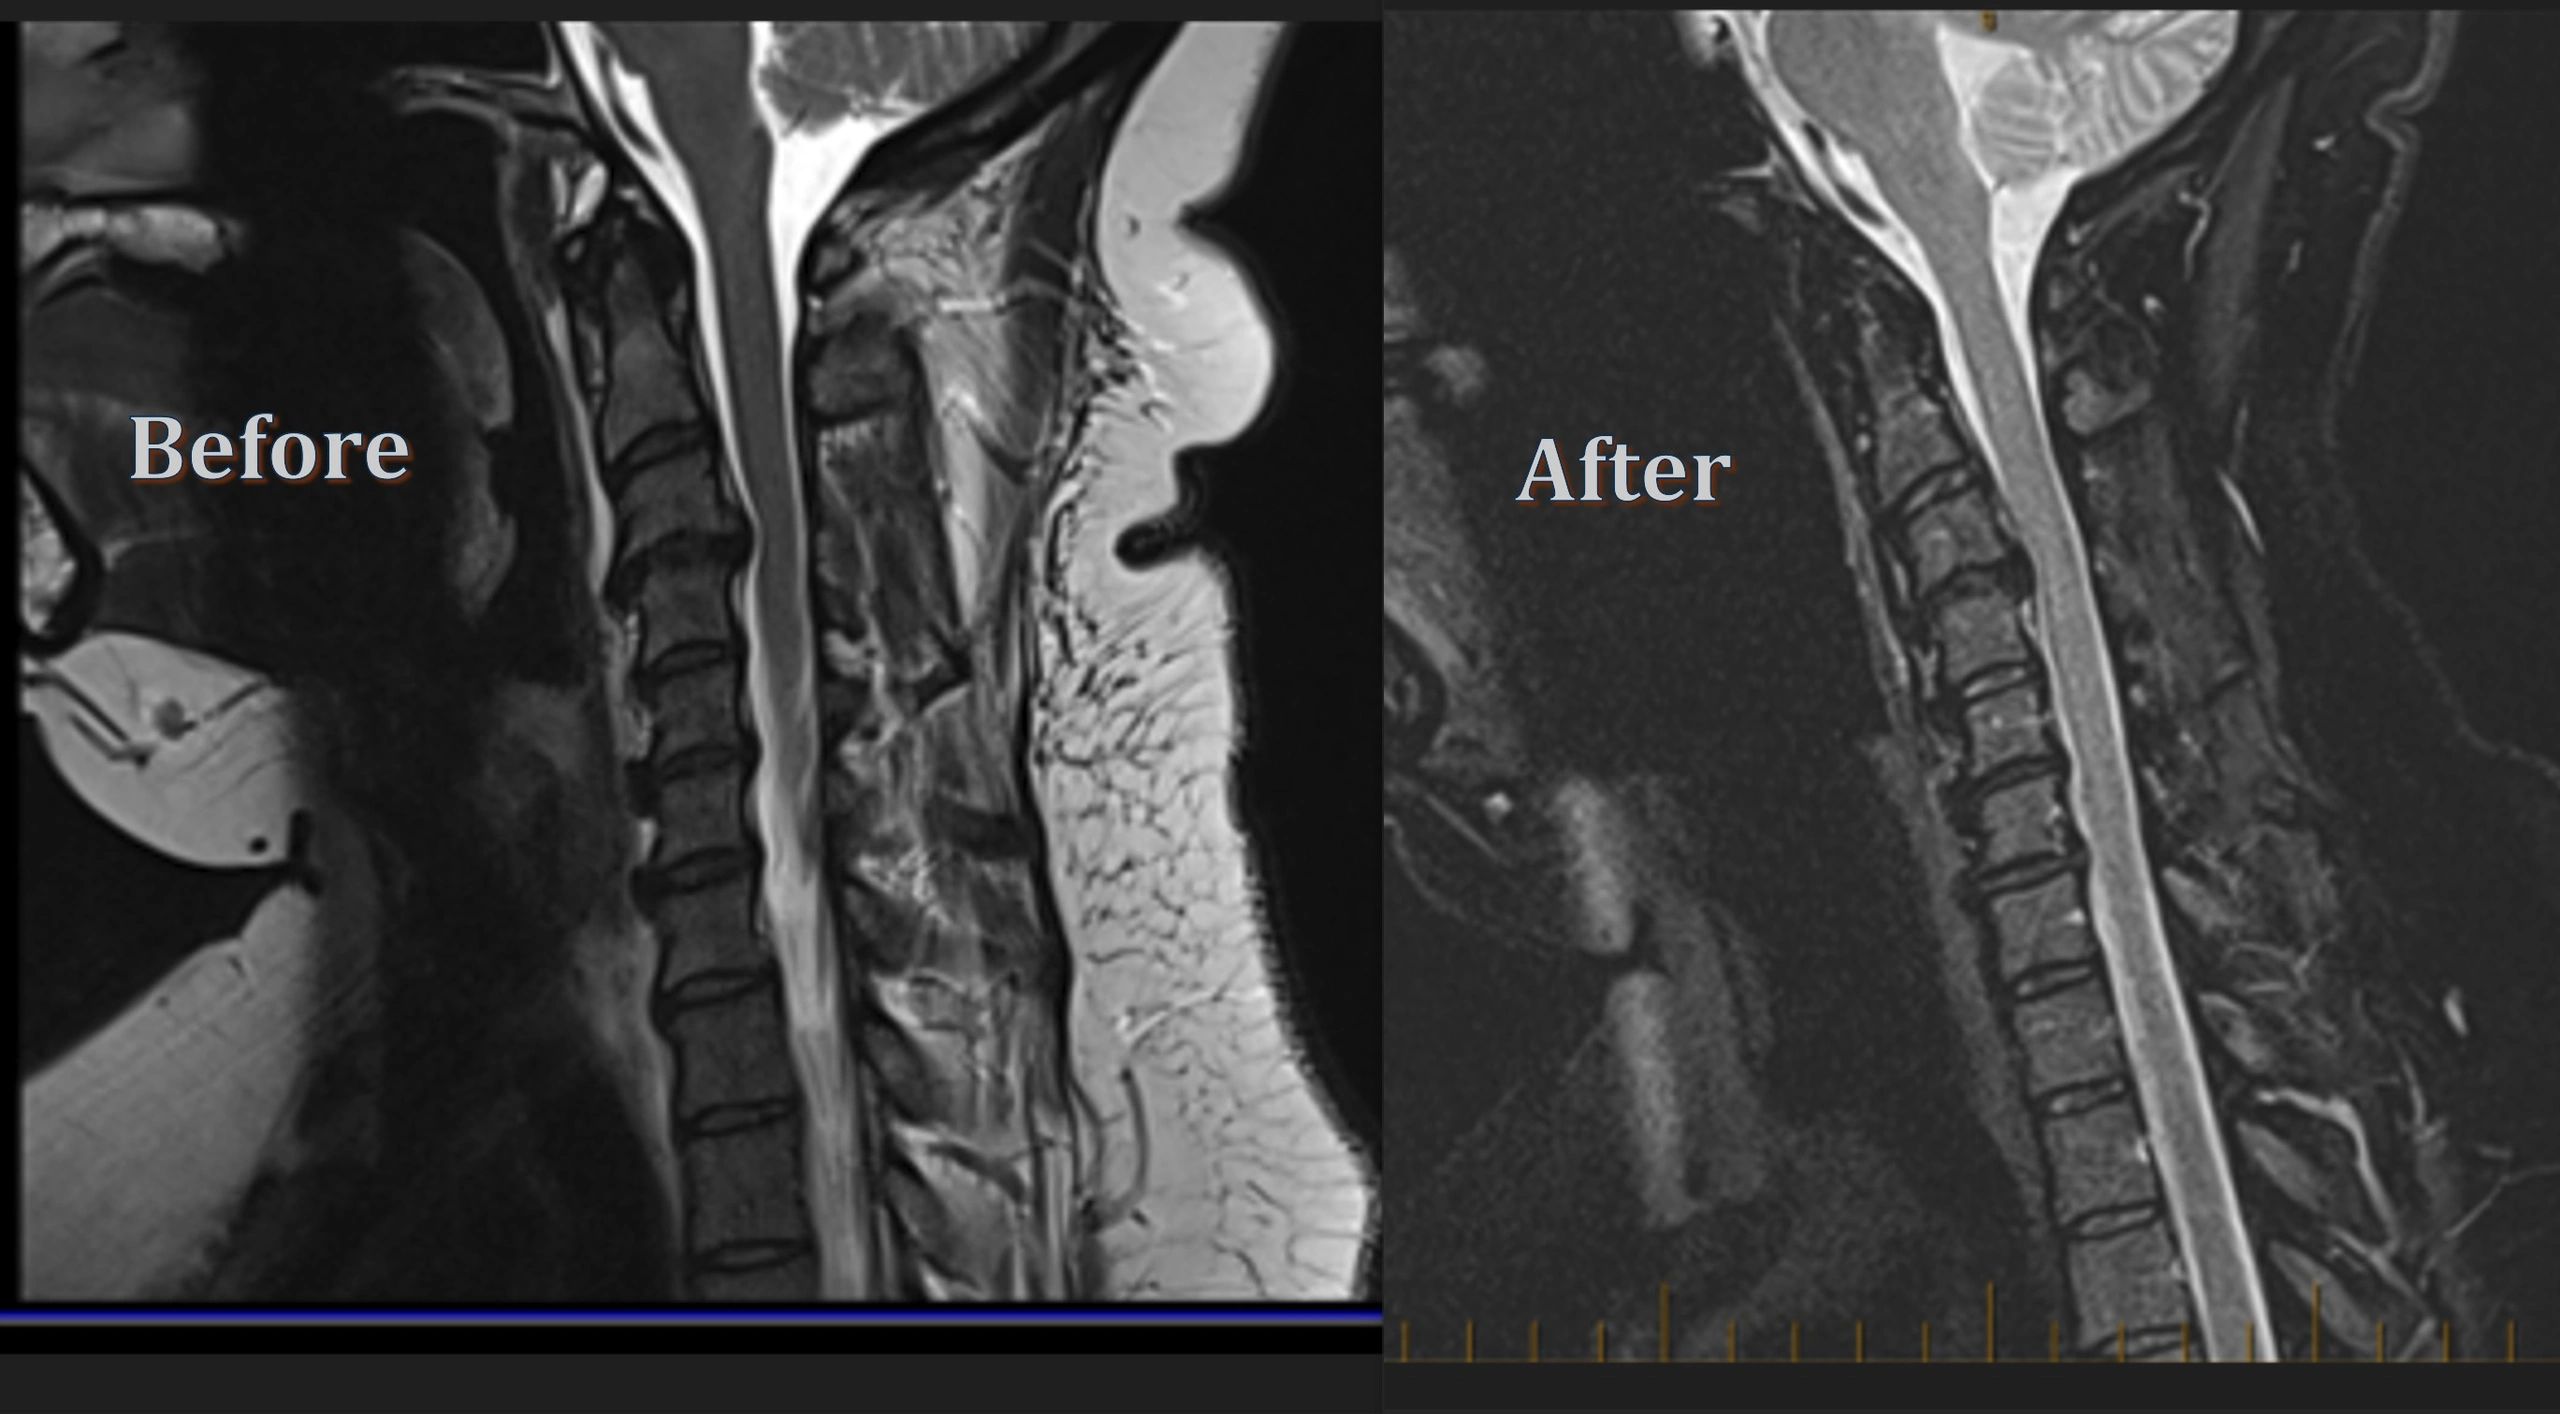

• Spinal cord injuries and stroke-related symptoms

Our Regenerative Therapy offers cutting-edge, umbilical cord-derived cellular therapy designed to support the body’s natural healing process. Our medical team, trusted by physicians across Texas and Oklahoma, provides the highest quality human cellular tissue products at an affordable price. With over 25 years of experience, we specialize in developing individualized treatment plans for arthritis, degenerative diseases, chronic illnesses, and soft tissue injuries. Every patient receives a thorough consultation and clear explanation of their options, ensuring personalized care and optimized outcomes.

Infinity Matrix Therapy can be used to support tissue regeneration in a variety of conditions, including: